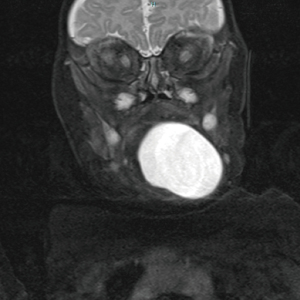

A total of five cases of head and neck FDCs were identified in the last 10 years at RCH. These are identified in Table 1. The mean age at diagnosis was 8.2 months. Two were female and three were male. Two cases were found in the floor of mouth (FOM), two in the base of tongue (BOT) and one in the uvula. Magnetic resonance imaging (MRI) was utilised in two cases (Figure 1), ultrasound (US) in one and two had no imaging. Four cases were treated with primary excision (Figure 2). One case in the FOM had attempts at excision, aspirations and sclerotherapy with definitive excision following. This patient had two previous attempts at sublingual gland excision at another site after initial presentation at four months of age. Following recurrence after attempted aspiration, he was referred to the RCH for further management. A multi-disciplinary meeting suggested possible lymphovascular malformation and so a decision for sclerotherapy was made. The cyst was injected with 100 mg of doxycycline under US guidance at 6 months of age. Despite this, the cyst recurred and definitive transcervical excision was performed at 8 months of age. Four cases had enteric epithelium found on histopathology, and one respiratory alone. Following excision, there was no reported recurrence of FDC, with three of five cases having a follow-up of over two years. Two cases did not report follow-up in the EMR as they were followed up privately.

| 1 | 10 | F | BOT | Feeding difficulty | MRI: T2 hyperintense lesion | Excision | Enteric | – |

| 5 | 8 | M | FOM | Feeding difficulty | MRI: T2 and T1 hyperintense | Multiple excisions and aspirations, and attempt at sclerotherapy | Enteric FDC and dermoid cyst | Residual cyst, nil recurrence at 6 months post excision |